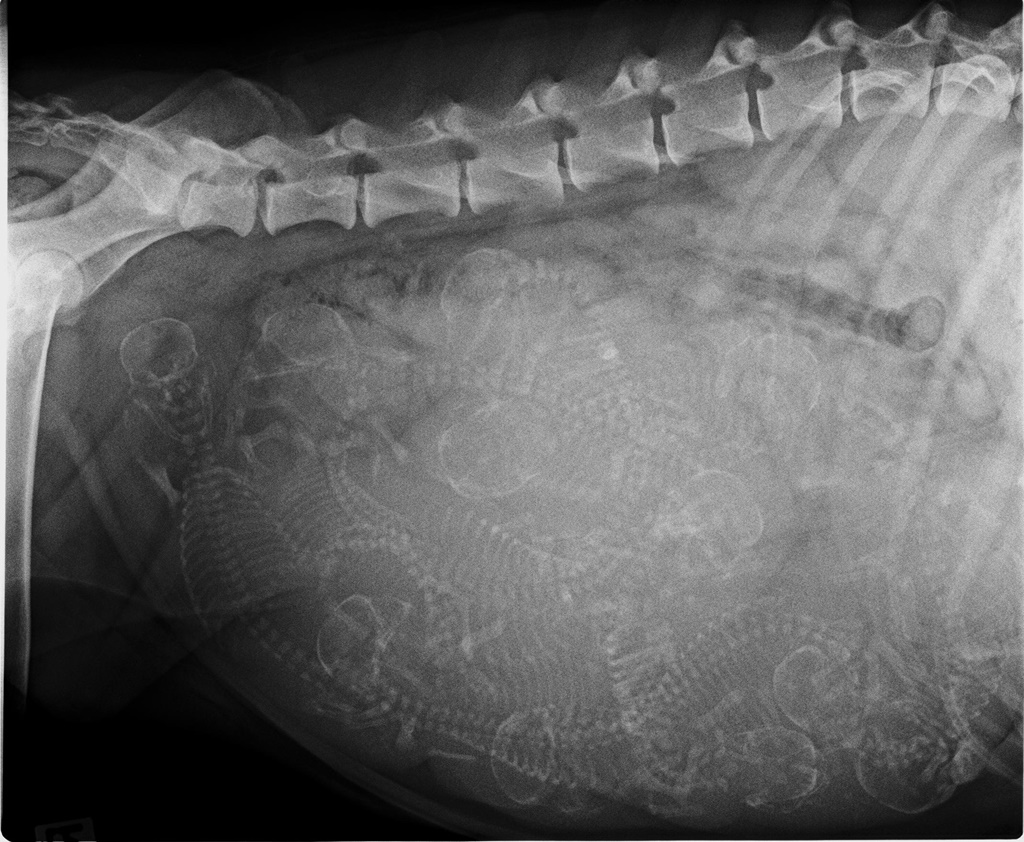

Bruna Röntgenkontrolle

Im Poker würde man sagen "FULL HOUSE"

Bruna und uns erwartet viel Arbeit.

Wir freuen uns!